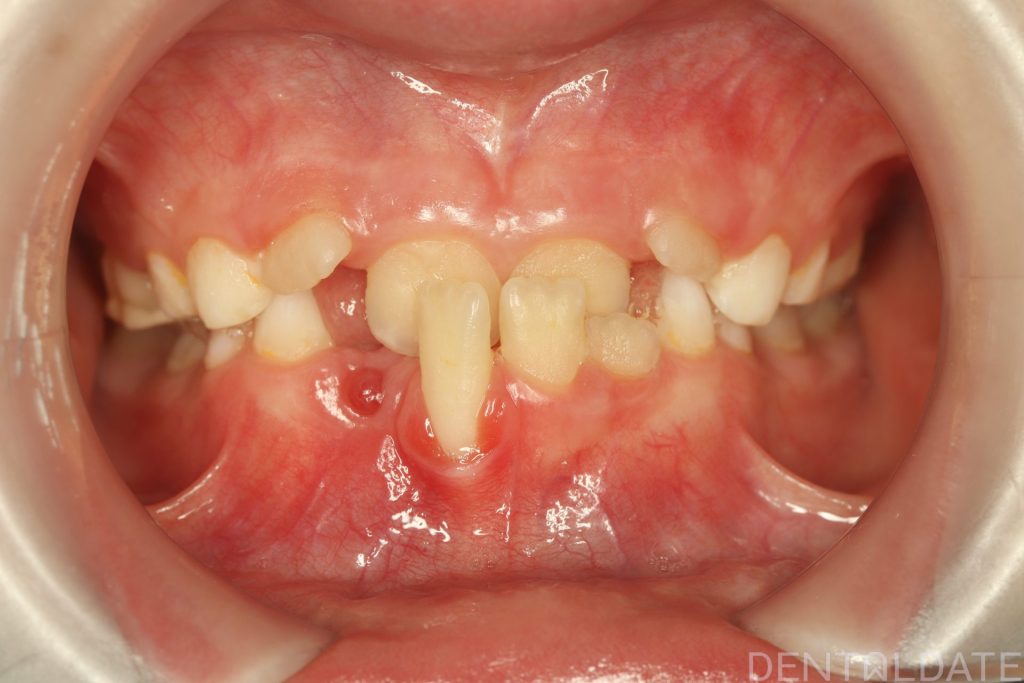

With a new treatment plan in place -the anterior bite was normalized within just one week.